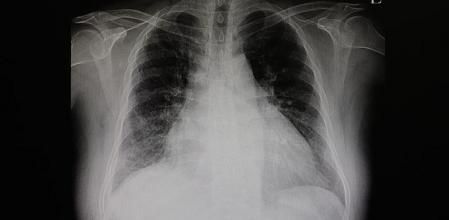

El diagnóstico de la insuficiencia cardiaca congestiva se basará en la descripción de síntomas; la historia clínica; el examen físico que incluya auscultación con estetoscopio, revisión de las venas del cuello y comprobación de retención de líquido en abdomen y piernas. También se solicitarán pruebas como:

- Radiografía de tórax para ver el estado de los pulmones y el corazón.